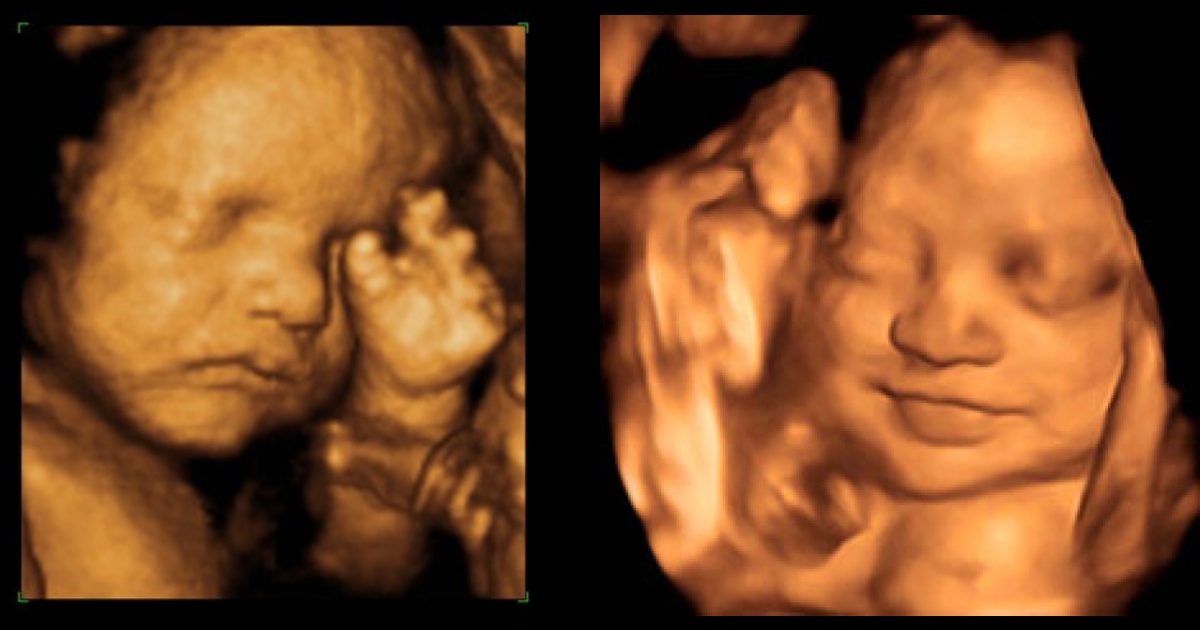

La expresión de la cara de un grupo de bebes aún no nacidos, captada a través de ecografías en 4D, constituye para un grupo de psicólogos la primera evidencia directa de que el feto reacciona a los sabores de los alimentos ingeridos por la madre.

Los fetos expuestos a la zanahoria mostraron más respuestas de "cara de risa", mientras que los expuestos a la col rizada mostraron más respuestas de "cara de llanto", explicó la citada universidad en un comunicado.

El equipo, encabezado por Beyza Ustun de la Universidad de Durham, destacó que fue "realmente sorprendente ver la reacción de los bebés no nacidos a los sabores de la col rizada o la zanahoria durante las exploraciones y compartir esos momentos con sus padres".

Las reacciones observadas en ambos grupos de sabores, comparadas con las de los fetos de un grupo de control que no se expusieron a ninguno de los sabores, mostraron que la exposición a una pequeña cantidad de sabor a zanahoria o col rizada "era suficiente para estimular una reacción”, indicó la universidad.